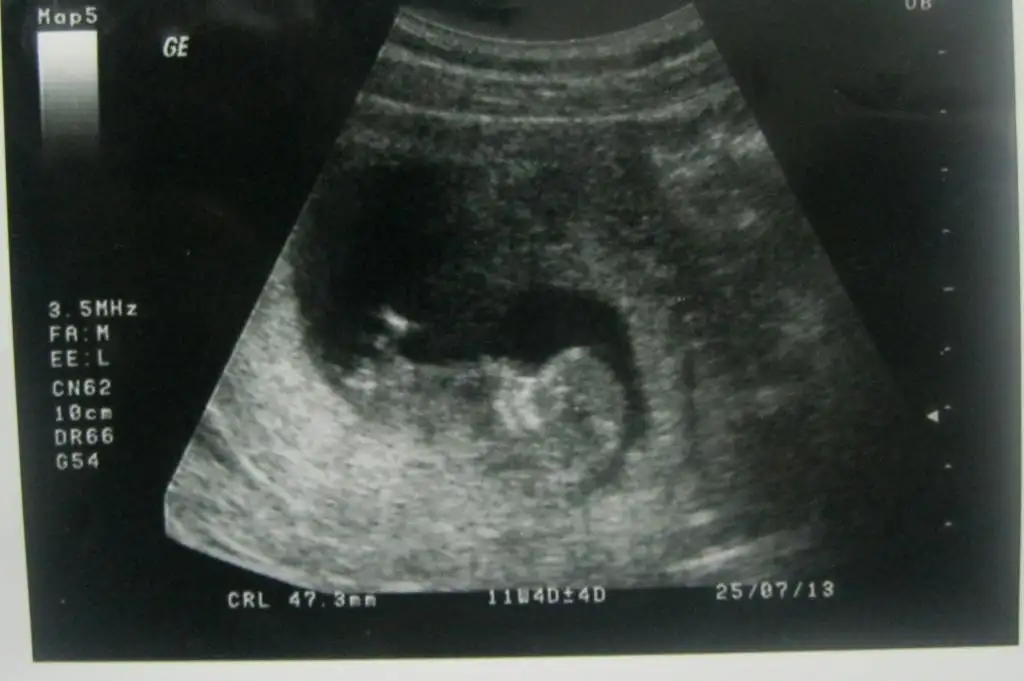

Görmemişler gibi çok resim ekledim ama belki görünmüyodur diye garanti olsun dedim :26: Resim 13. haftadan